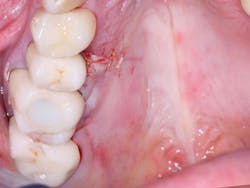

Figure 8: Closed wound of patient in Figure 7 healed rapidly with diminishing pain after 24 hours.